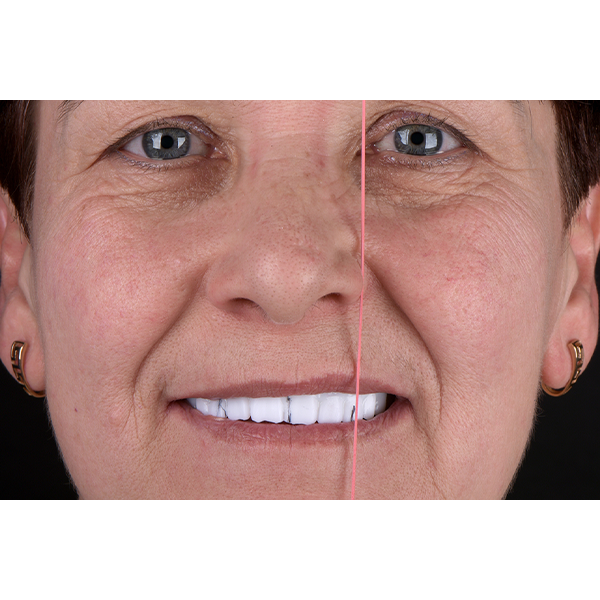

Après la mise en moufle et l'ébouillantage, les dents ont été repositionnées, conditionnées et des caractérisations blanchâtres, pourpres, orange clair, bleues et roses ont d'abord été réalisées au niveau du le bouclier labial. La base a ensuite été incrustée de résines pour prothèses de couleurs orange-rouge, rouge foncé, rouge clair, rose et rose foncé, et tous les polymères à chaud ont été pressés en une seule fois. Après le stockage sous pression, les prothèses finies ont été démouflées, finies et polies. La stratification anatomique tridimensionnelle de VITAPAN EXCELL en masse d'émail, de collet et de dentine avait un aspect absolument naturel dans l'anatomie muco-gingivale reproduite de la base prothétique. Le patient a pu s'habituer rapidement à sa nouvelle prothèse, notamment grâce à l'effet esthétique réussi. Après une courte phase d'adaptation et des corrections minimes dans l'environnement biodynamique, il s'est très bien débrouillé avec sa première restauration prothétique amovible complète et en était pleinement satisfait.